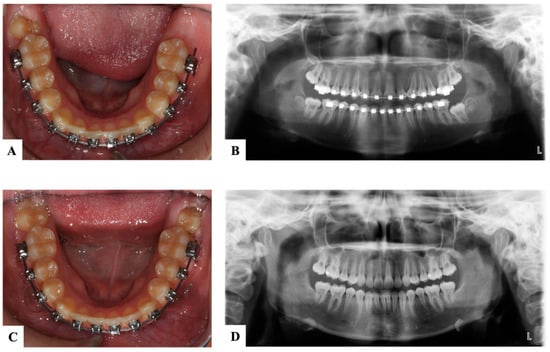

10. Ectopic Second Permanent Molars